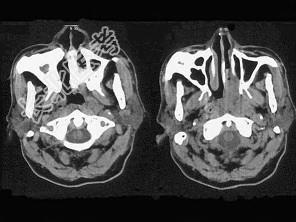

- 单项选择题男,64岁, 间断性流鼻血一年余,近1个月加重, CT如图所示,最可能的诊断为 ( )

A、鼻咽部腺样体增生

B、鼻咽纤维血管瘤

C、鼻咽部恶性淋巴瘤

D、鼻咽部淋巴组织增生

E、鼻咽癌